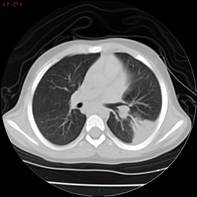

Al mes de haber suspendido tratamiento, presenta RAE: 5.220/mm3 por lo que reinicia meprednisona 1 mg/kg/día vía oral. Con laboratorio control a los 11 días y RAE en descenso se decide descender glucocorticoide para evitar efectos adversos a largo plazo hasta suspenderlo y asociar hidroxiurea a 15 mg/kg/día vía oral como ahorrador de glucocorticoide. Se cita al paciente cada 10 días para evaluar curva de descenso de RAE. En los controles posteriores el paciente comienza a desmejorar, presentando anemia con requerimiento transfusional, RAE: 5.600/mm3, ERS y PCR en ascenso, agrega síndrome febril intermitente y compromiso respiratorio. Se diagnostica neumonía unifocal izquierda. Se realizaron hemocultivos, que fueron negativos, y aspirado para gérmenes comunes y COVID. que fue negativo. Se realiza TAC de tórax donde se observa imagen compatible con neumopatía infiltrativa. Se realiza lavado broncoalveolar, observándose infiltrado eosinofílico 60% con cultivo negativo para Aspergilosis asociada a eosinofilia en contexto de tratamiento inmunosupresor.